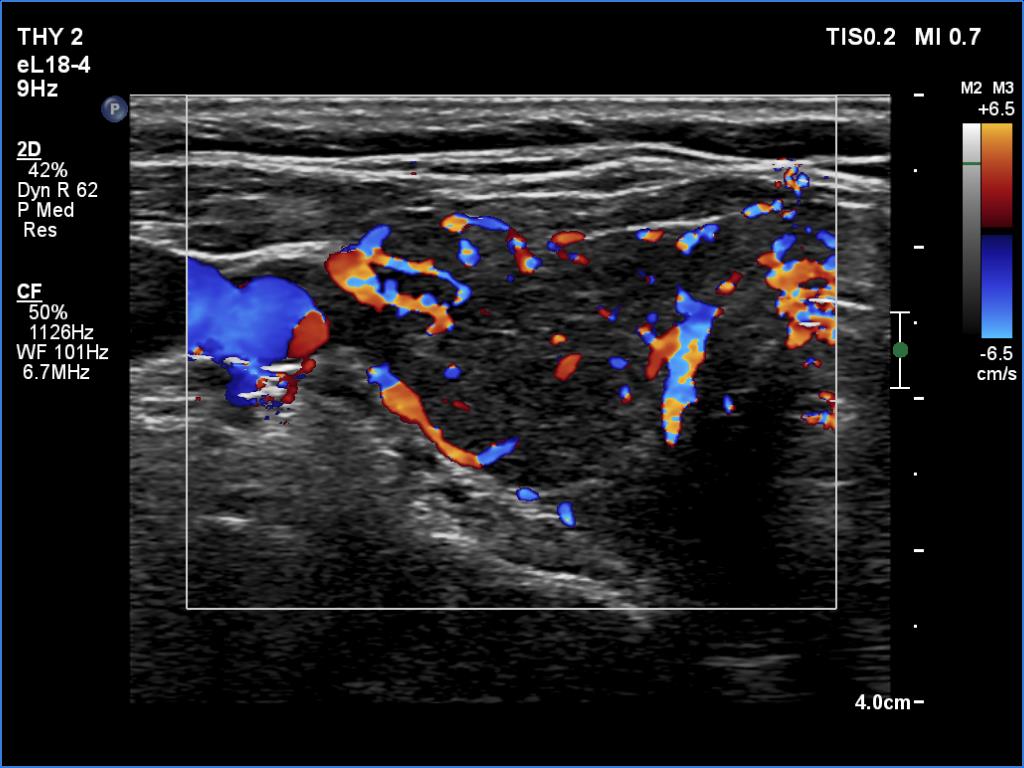

Graves' disease - case 940 (ultrasonographic picture 3)

Right lobe, transverse view, color Doppler mode. The vascularization is increased.